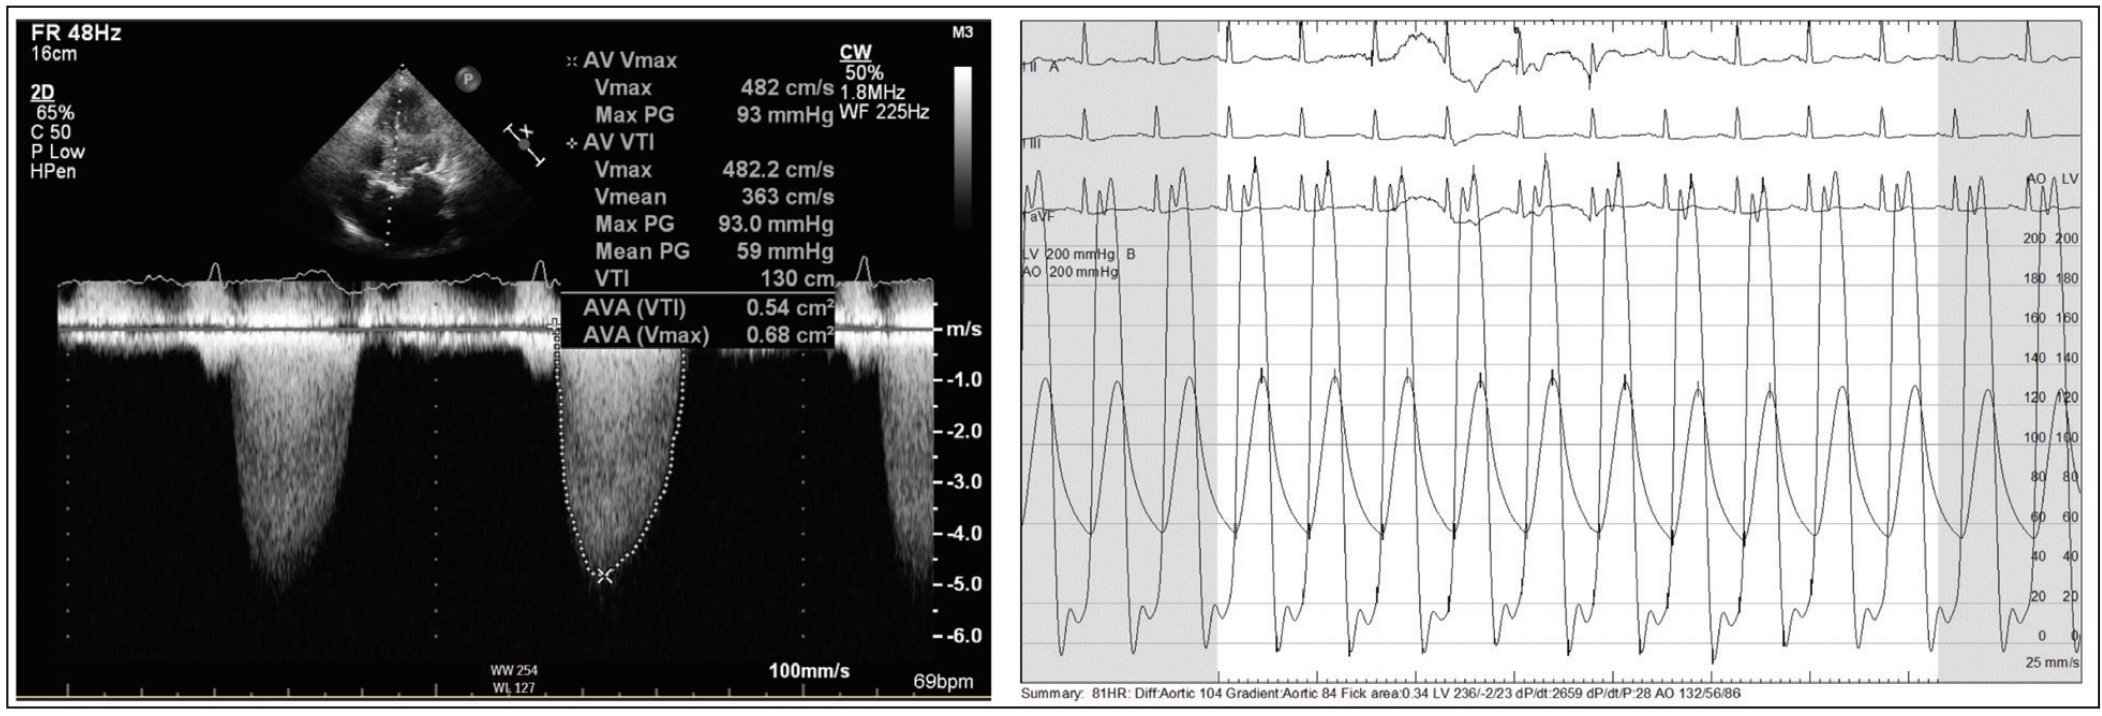

An 84-year-old woman was referred for transcatheter aortic valve replacement (TAVR) without cardiovascular risk factors, except for remote tobacco abuse more than 30 years earlier. She had been diagnosed with aortic stenosis (AS) and managed conservatively by means of annual echocardiographic assessment for the previous 5 years. Approximately 2 weeks prior to consultation, she was admitted with flash pulmonary edema that was treated with diuretics. At the time of consultation, the patient was stable without angina or lightheadedness. The patient lives by herself and is able to perform her activities of daily living. Her medical history included lung cancer (stage IB) treated 8 years earlier with image-guided robotic stereotactic radiosurgery (CyberKnife, Accuray Incorporated), chronic lung disease with an FEV1 40% of predicted without improvement with bronchodilators and an O2 saturation decrease of 89% after walking 700 feet, hypertension, and osteoporosis. Her renal function was preserved with a glomerular filtration rate of 84 mL/min and a creatinine of 0.56 mg/dL. Physical examination revealed that she was a thin and frail-appearing woman with a body mass index of 22.26 kg/m2 (height, 152 cm; weight, 51 kg) who uses a walker to ambulate. The lungs were clear to auscultation. She had a 2/6 crescendo-decrescendo systolic murmur that obscured S2. Echocardiography revealed severe AS with a valve area of 0.58 cm2, aortic maximum/mean pressure gradients of 108.6/72 mm Hg, and a peak aortic valve velocity of 5.21 m/s (Figure 1). There was no aortic regurgitation. The ejection fraction was preserved (65%) and there was severe mitral annular calcification causing mild mitral stenosis (valve area, 1.8 cm2). Coronary angiography demonstrated nonobstructive coronary artery disease. Of note, coronary angiography was performed via right transradial access and significant subclavian tortuosity was encountered while advancing the J-wire, but the vessel straightened, posing no added difficulties to performing the procedure (Figure 2). Hemodynamic assessment showed a peak aortic gradient of 104 mm Hg with an aortic valve area of 0.34 cm2 (Fick principle) (Figure 1). The pulmonary arterial pressure was 48/18/(29) mm Hg. Based on the type of procedure and patient data, the Society of Thoracic Surgeons (STS) predicted risk of mortality was 11.6%.